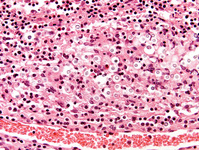

Biópsia do cérebro do lobo temporal direito: uma exibição aumentada de um vaso sanguíneo circundado por um infiltrado inflamatório acentuado também é observada. Estudos de reação em cadeia da polimerase da amostra da biópsia foram positivos para infecção por vírus Epstein-Barr (EBV)

Do acervo pessoal de Catalina C. Ionita, MD; usado com permissão

Veja esta imagem em contexto nas seguintes seções: